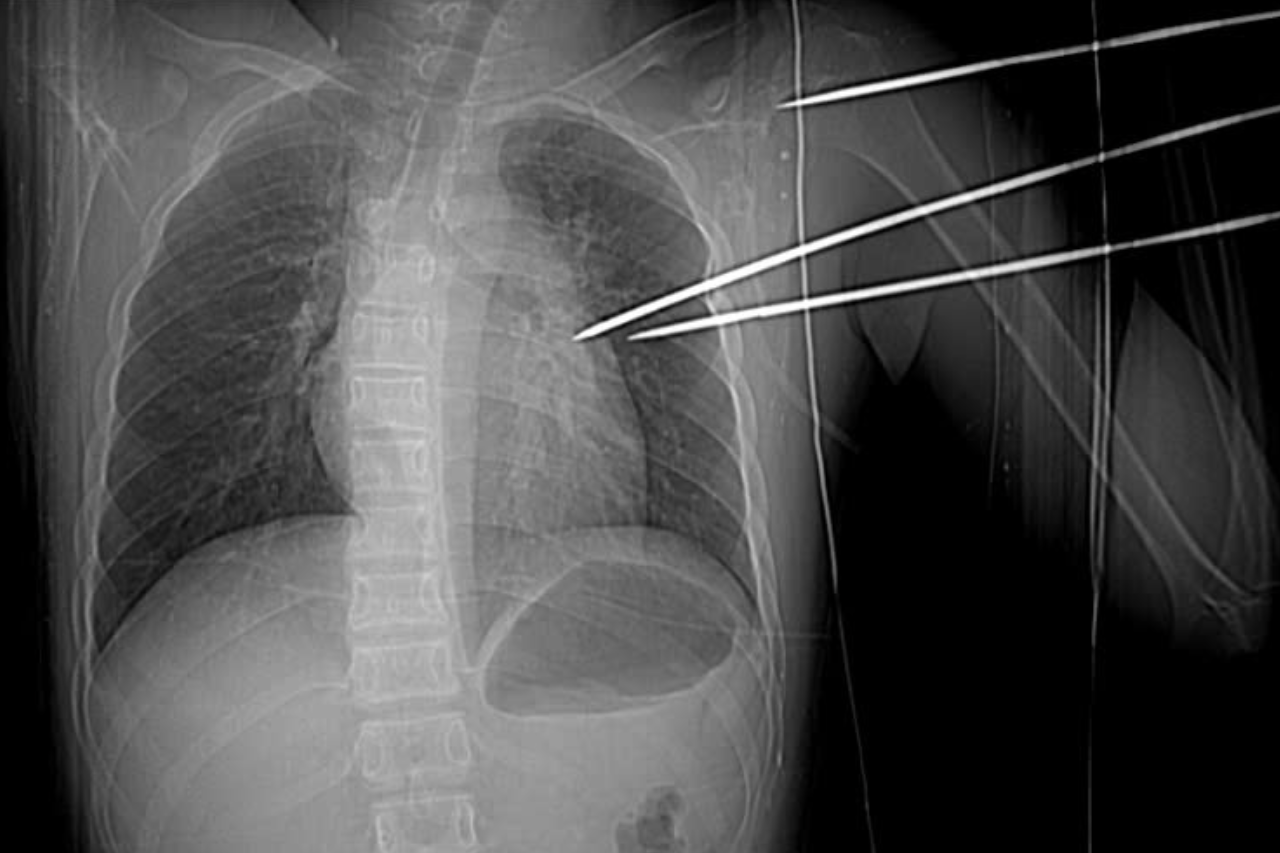

Hình ảnh chụp X-quang và cắt lớp vi tính cho thấy dị vật xuyên qua mặt sau vai trái và mô thùy trên phổi trái, đâm vào thành bên thất trái của tim, gây tràn máu màng tim.

Bác sĩ Nguyễn Văn Đàn, Khoa Ngoại Tim mạch và Lồng ngực, cho biết bệnh nhân được đưa vào phòng mổ cấp cứu. Các bác sĩ tiến hành mở ngực, ghi nhận khoang màng tim có khoảng 150g máu cục do dị vật gây vết thương ở thành bên thất trái.

Khi mở màng phổi kiểm tra, phát hiện dị vật cũng xuyên qua nhu mô phổi trái, gây tràn máu khoang màng phổi. Tổng lượng máu mất của bệnh nhân ước tính khoảng 500-600ml.